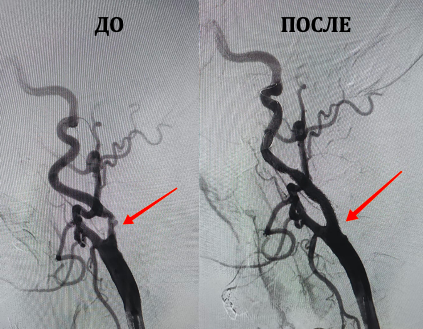

«УЗИ сосудов шеи пациента показало стенозы и атеросклеротические бляшки в сонной артерии пациента. Ангиографическое исследование подтвердило, что сосуды шеи «забиты» и риск инсульта крайне высок», – рассказал врач-ангиохирург, заместитель директора по высоким медицинским технологиям ММЦ имени Н.И.Пирогова ФМБА России Михаил Воронин.

Он объяснил, что левое и правое полушария головного мозга снабжаются сонными артериями. При ее атеросклеротическом поражении возникает высокий риск эмболии – когда частички атеросклеротической бляшки с кровотоком попадают в головной мозг. Это приводит к артериальной недостаточности, или, проще говоря, к инсульту.

Если говорить о болезнях сердечно-сосудистой системы, смертность от острого инсульта занимает второе место после смерти от острой коронарной недостаточности. При выявлении такого поражения на сонных артериях в 90% случаев выполняется имплантация каротинного стента, что и было проведено. В результате пациент избежал обширного полушарного инсульта.